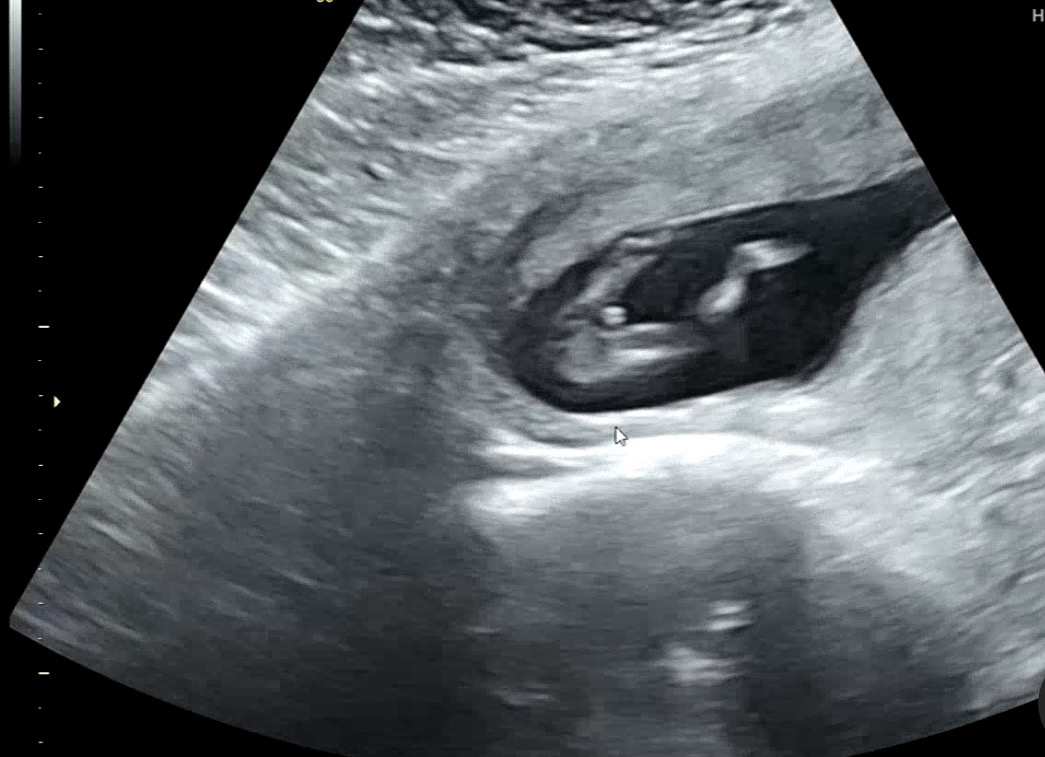

이정도면 아들이죠?

첫째 아들인데.. 둘째도 아들 확정일까요..ㅎ 12주 3일차에요 의사선생님도 아들같다고하시네요..!